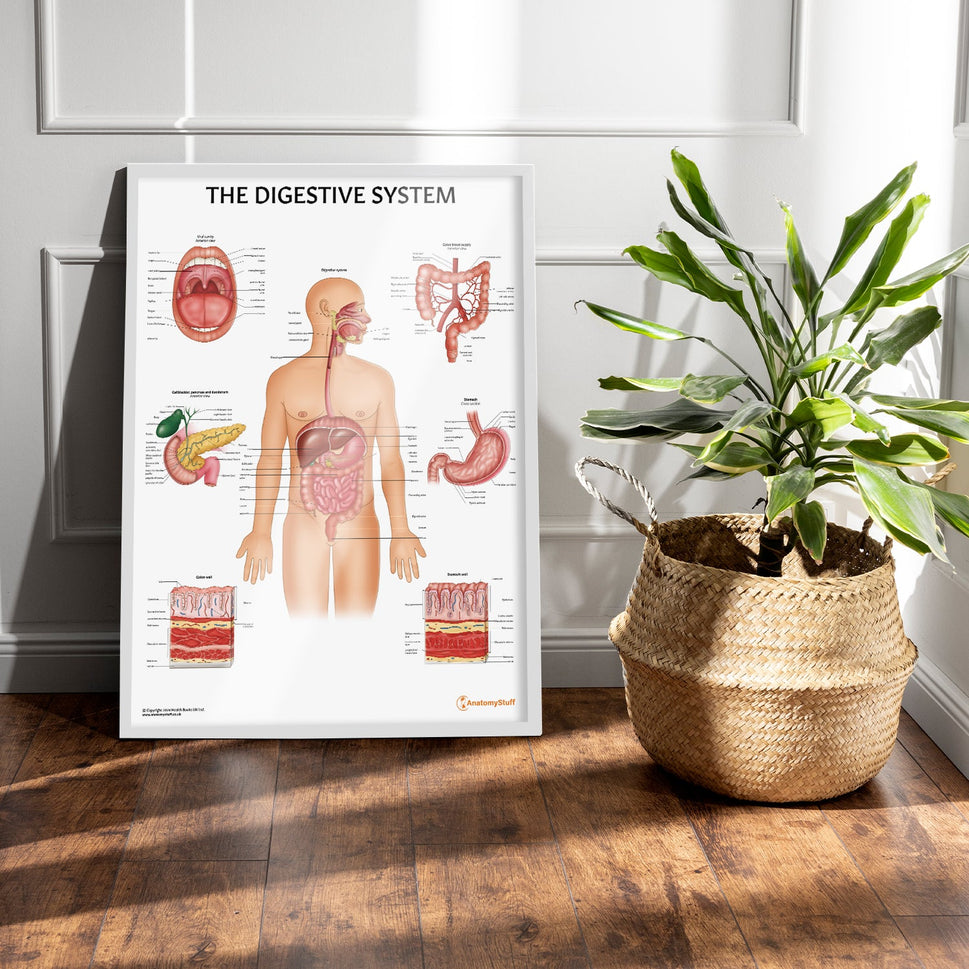

Enhance medical education with our collection of digestive system anatomical models including the stomach, liver, gallbladder, pancreas & colon models. Discover the anatomy of healthy organs as well as common gastrointestinal diseases such as stomach ulcers, gallstones and liver cirrhosis. Our digestive system anatomy posters are ideal for study and patient education.

At AnatomyStuff we stock a diverse range of digestive system anatomical models to suit your training needs. From budget models and affordable medical education posters to highly advanced 3D printed bowel models, you can transform medical training and patient education. As well as our own exclusive collection, we are proud resellers of 3B Scientific, Anatomy Lab, Denoyer-Geppert Science Company, ESP Models, Erler Zimmer and GPI Anatomicals. Explore our exclusive collection of digestive system anatomy charts, posters, fine art prints and digital anatomy study guides. Discover the anatomy of key organs like the liver, stomach, pancreas and bowel as well as the pathophysiology of common conditions like peptic ulcer disease, coeliac disease, IBD and much more. We have anatomy posters suitable for school children all the way up to medical degree level. From a liver anatomy poster to a digital study guide all about common GI disorders, find exactly what you need right here to enhance medical training and patient education.